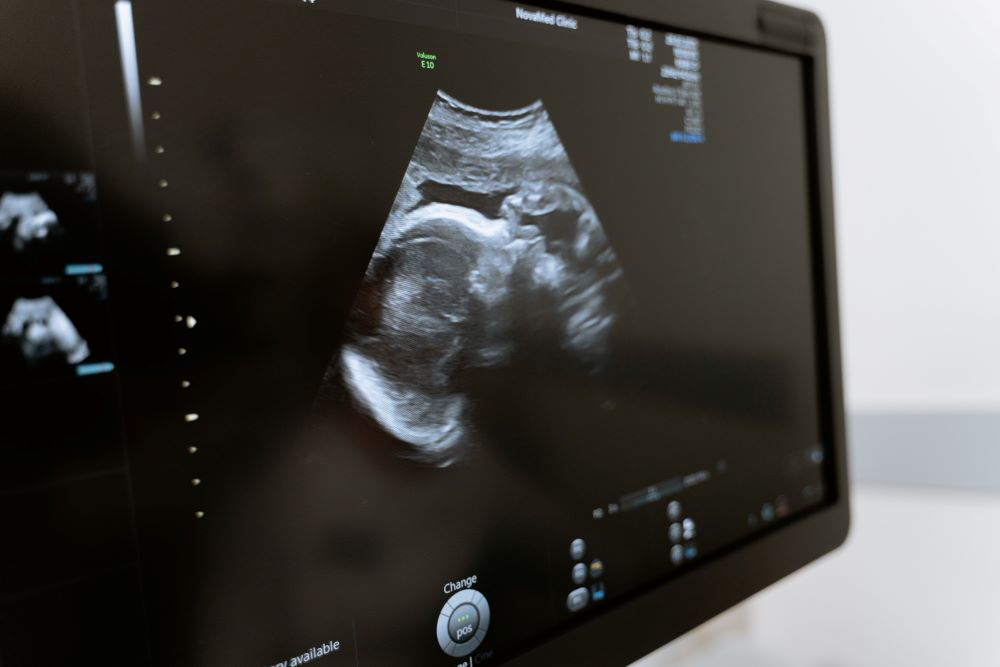

A high-risk pregnancy is any pregnancy that is flagged as potentially troublesome for a variety of reasons. It could be something with the overall health of the mother that causes it to be considered high-risk, or it could have to do with something that is seen early on in the monitoring of the growth of the baby. Whatever the case, high-risk pregnancies always come along with extra attention from the medical team to make sure both mother and baby are given the best possible chance of good health in the end. Typically, OBGYNs will require additional appointments and monitoring to ensure everything stay on track.